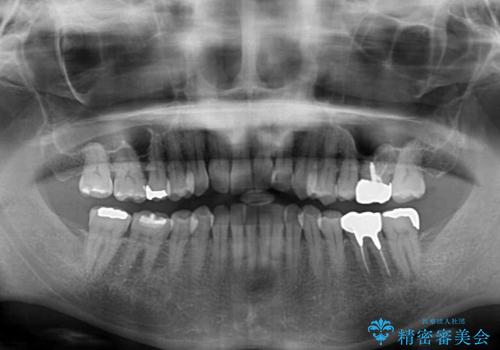

- 前歯のクロスバイトが気になり、インビザラインによる矯正治療を希望して来院された患者様です。

上顎側切歯(上の真ん中から2番目の歯)が舌側転位している場合、インビザラインでは仕上げきれないことが多く、更には無理して動かそうとすると歯髄壊死を起こすリスクが高いと言われています。

インビザラインで歯列を移動する前に、上顎前歯をワイヤー矯正で整え、その後上下歯列をインビザラインにて矯正治療を行うこととしました。